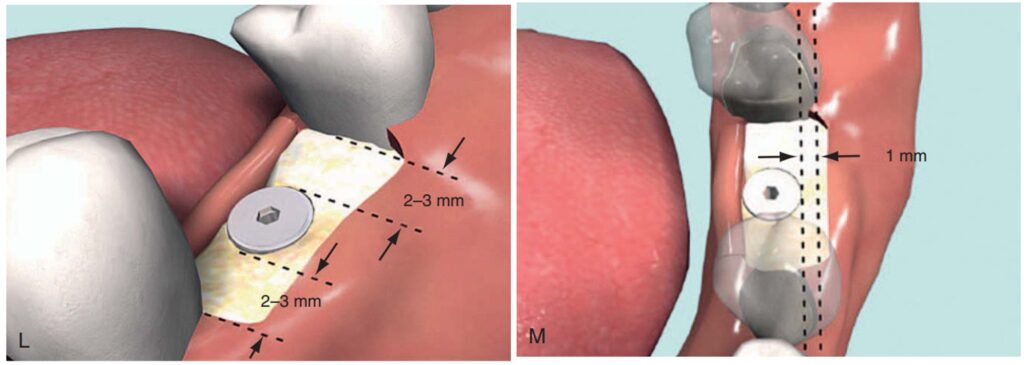

Dụng cụ hướng dẫn định vị Implant

Giúp xác định đúng vị trí đặt Implant và lựa chọn đường kính Implant tối ưu nhất (H2.18). Bộ hướng dẫn ITT gồm có:

– Tấm Titan, giúp hướng dẫn đường kính và vị trí của 1 – 2 Implant.

– Pin đo đạc có phần mở rộng, giúp hướng dẫn đường kính và vị trí Implant ở bệnh nhân không răng.

– Pin song song, để xác định độ song song của Implant.

– Cán của tấm Titan, giúp cầm nắm và đặt tấm Titan vào trong miệng 1 cách an toàn.